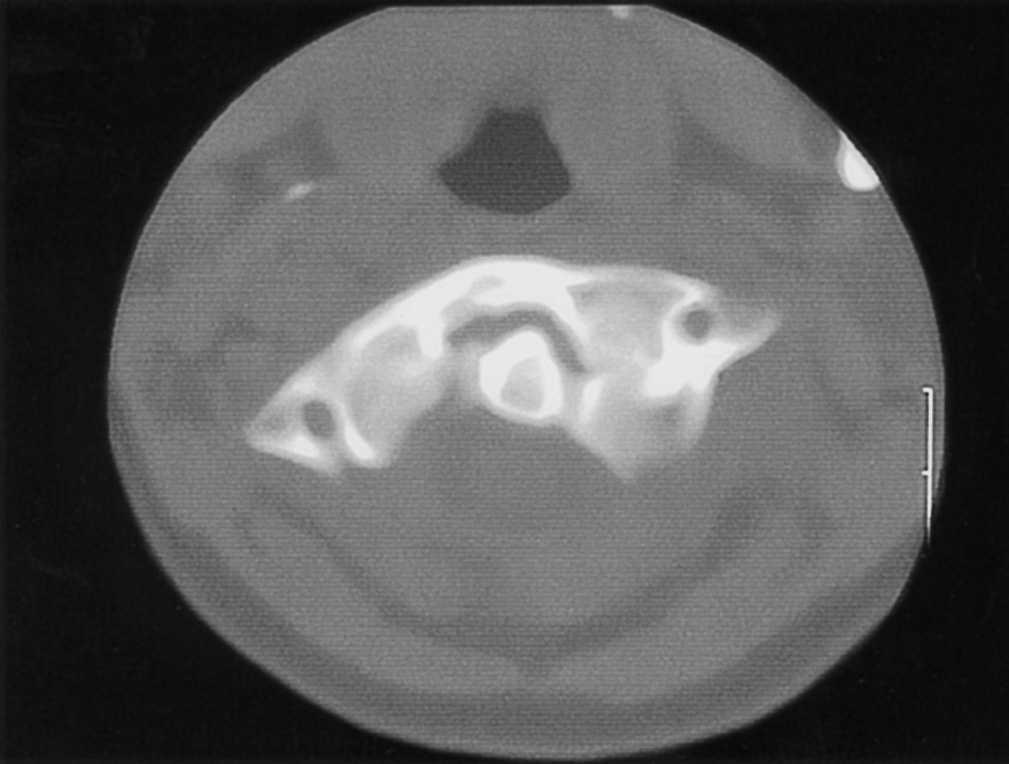

Paciente varón de 9 años con tortícolis asociada a fractura de clavícula por una caída en gimnasia. Tratado en su ciudad de origen mediante vendaje en 8 para la fractura de clavícula, y relajantes musculares y fisioterapia, fue remitido a nuestro centro a las 15 semanas por persistencia de la sintomatología (fig. 1). Las radiografías eran poco demostrativas, por lo que se practicaron estudios mediante TAC y RMN diagnosticándose de SRCAA tipo I3, con una divergencia C1-C2 de 42° (fig. 2); se instauró tracción halo-gravedad progresiva hasta un peso de 7 kg, en que se detuvo por aparición de disartria (17 días de tracción), con una movilidad rotacional levemente disminuida, la TAC de control mostró una divergencia residual de 11°, por lo que para evitar la recidiva se efectuó un artrodesis posterior C1-C2 in situ con injerto de cresta ilíaca (fig. 3), manteniendo la tracción durante la intervención e inmovilizándose con halo-yeso 3 meses. Una vez retirada la tracción, la disartria remitió espontáneamente. Quince años después, el paciente presenta una movilidad cervical prácticamente normal, con una limitación de la rotación izquierda de 10°.

Figura 2. Imagen de la tomografía axial computarizada (TAC) del paciente n.O 1 que muestra el método de medición, con una divergencia atlanto-axial de 42°.

El diagnóstico radiológico es difícil, ya que la deformidad y el dolor impiden obtener buenas proyecciones, así en la radiografía anteroposterior simple se superpone la cabeza, y en la lateral se puede observar una falta de paralelismo entre el cráneo y la columna; la radiografía transoral de odontoides puede ser de gran valor, mostrando una asimetría entre el diente del axis y las masas laterales del atlas con posible pinzamiento de las facetas8. Se ha sugerido la utilización de la TAC dinámica, con rotación a izquierda y derecha de la cabeza, pero en situación de SRCAA la movilización es dolorosa, por lo que difícilmente se obtendrá la cooperación del paciente, pudiendo llevar a confusión en el diagnóstico13. En una tortícolis aguda no parece estar indicado el estudio con TAC14,15, pero en casos persistentes con sospecha de SRCAA es muy útil para confirmar el diagnóstico, ya que mostrará la divergencia rotacional C1-C2 que se puede cuantificar midiendo la angulación existente entre las líneas que unen las apófisis transversas del atlas y del axis (fig. 2)16. En la TAC tridimensional se puede apreciar la deformidad rotacional con el desplazamiento completo de las facetas articulares, la situación asimétrica de la odontoides en el arco anterior del atlas --que asimismo puede orientar sobre la integridad del ligamento transverso-- y el desplazamiento de la espinosa de C24. La RMN es un buen complemento, ya que puede informar de interposición de partes blandas7, así como de la posible lesión del ligamento transverso17, por lo que en caso de duda puede indicar la necesidad de estabilización quirúrgica. En nuestra serie, ante una sospecha de SRCAA, se utilizó la TAC simple como método diagnóstico (fig. 2 y 4A), completándose en el tercer caso con reconstrucción tridimensional (fig. 4B) en la cual fueron muy evidentes las alteraciones torsionales del complejo atlantoaxial.